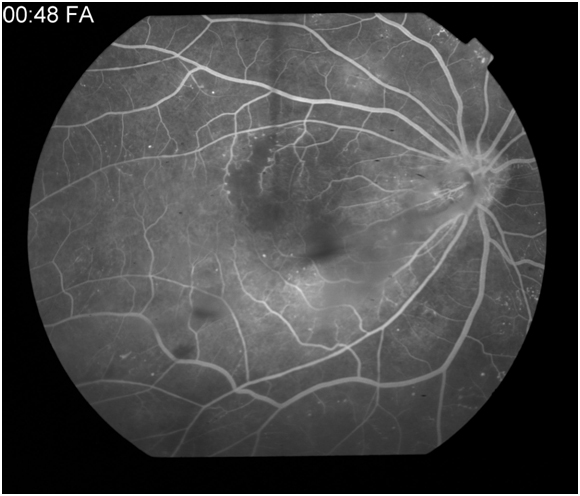

Figure 5A: Peak phase angiogram in a patient with diabetes demonstrates areas of hyporfluorescence in the superior macula secondary to a vascular filling defect as well as hyperfluorescent microaneurysms. 5B: Late phase angiogram demonstraing diffuse macular leakage from microaneurysms, vascular leakage, incompetent retinal pigment epithelium, and tractional affect from a preretinal membrane.